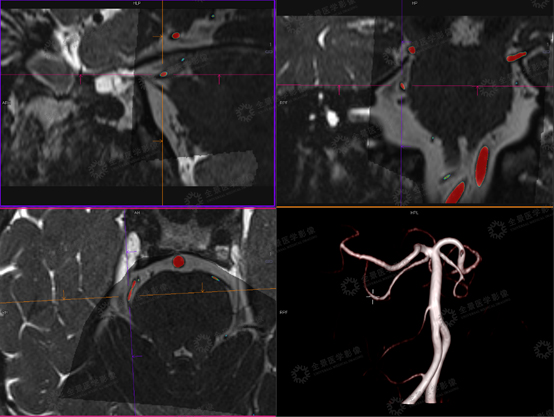

上海全景医学影像诊断中心利用西门子3.0T高场强磁共振扫描仪,采用MRTA序列为:3D TOF MRA序列联合T2 space序列,利用融合校准技术,形成多模态融合MRTA图像,可做到简化阅片,同时可以清晰显示三叉神经与责任血管的解剖关系,明确责任血管来源,并可以利用三维重建进行空间定位,对临床进行术前诊断、术前评估和指导手术方案具有重要的意义。

病史:患者,男,69岁,右侧三叉神经痛治疗后,再次右侧面部疼痛2月